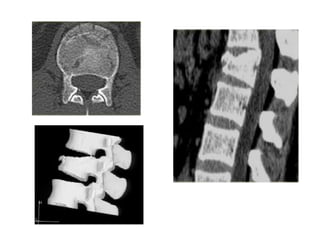

Burst fractures

• 15 % of TL#s

• Anterior& middle column failure.

(Axial compression)

• Most common at T/L junction

• Neurological deficit.

Burst fractures • 15% of TL#s • Anterior& middle column failure. (Axial compression) • Most common at T/L junction • Neurological deficit.